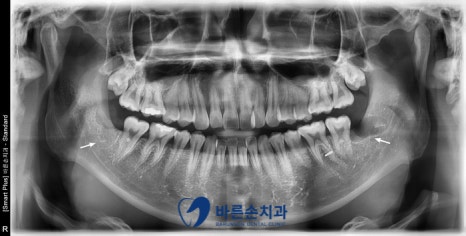

안녕하세요. <의정부 바른손치과>입니다.! 오늘은 사랑니 발치 증례를 보여드리도록 하겠습니다. 이 환자분은 20대 중반의 남성분으로 양쪽 아래 사랑니가 아프셔서 발치를 하러 저희 바른손치과를 찾아주셨습니다. 엑스레이 사진에서 보시면 양쪽 위 아래 사랑니가 모두 있고 왼쪽 아래 사랑니가 누워서 부분적으로 매복되어 있는 상태입니다. 구강 내 사진입니다. 좌우 모두 사랑니 머리가 일부만 구강내로 맹출해있습니다. 이런 경우 음식물이 끼기 쉽고, 칫솔로 제거도 쉽지가 않습니다. 그래서, 잇몸이 부어 피가 나고 아픈 경우가 자주 일어 날 수 있고 나아가 앞에 있는 치아 까지 썩게 할 수 있습니다ㅜㅜ 이런 경우엔 사랑니 발치를 통해 구강 환경 개선을 해야합니다!!! 사랑니 발치에 앞서 3D CT 촬영을 하였습니다. 사랑니의 형태와 위치, 아래턱뼈에 있는 하치조신경관의 해부학적 위치를 정확히 확인 후 발치에 들어갑니다. 오른쪽 아래 사랑니를 발치하고 엑스레이를 찍어 확인하였습니다. 왼쪽아래 옆으로 누워있는 사랑니도 발치를 하였습니다. 환자분께서는 문제를 일으키던 사랑니를 뽑으니 홀가분하고 시원하다고 하셨습니다.!! 약 일주일 정도 회복기간을 가지시면 사랑니 부위의 잇몸은 어느정도 아물게 됩니다. 사랑니 발치 더이상 두려워 하지 마시고 <의정부 바른손치과>에서 뽑으세요^^ |